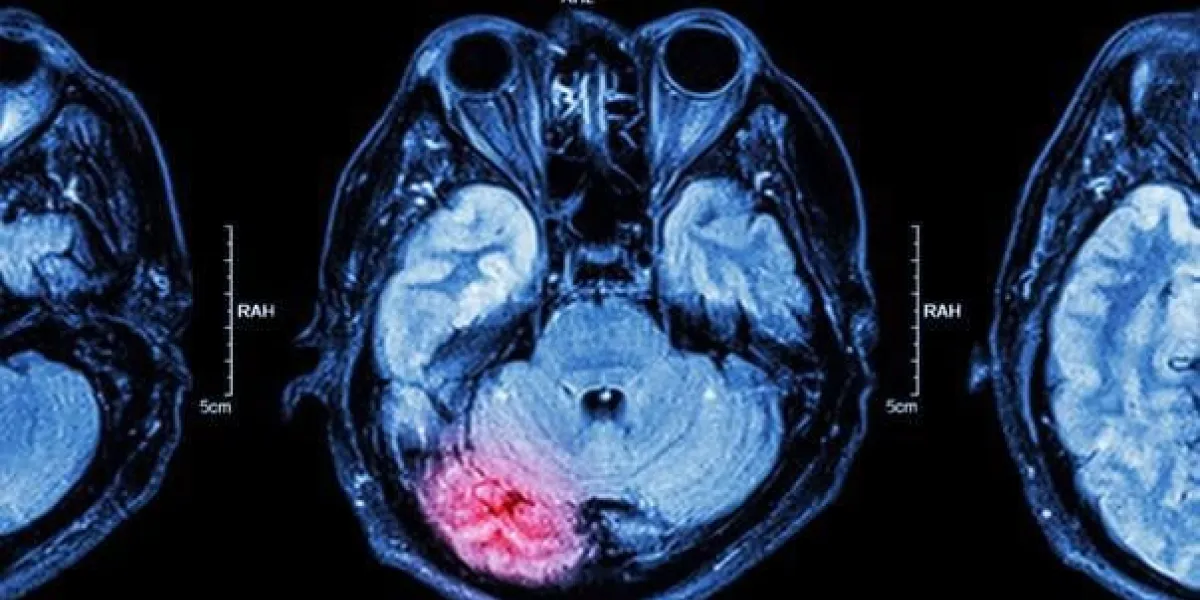

La maladie de Parkinson est une maladie neurodégénérative chronique qui affecte principalement le système nerveux moteur, provoquant une diminution progressive de la coordination et du contrôle des mouvements. Elle est causée par la mort progressive des neurones producteurs de dopamine dans le cerveau. Les symptômes de la maladie de Parkinson peuvent inclure des tremblements, une rigidité musculaire, des mouvements lents, une perte d'équilibre et des troubles du sommeil.